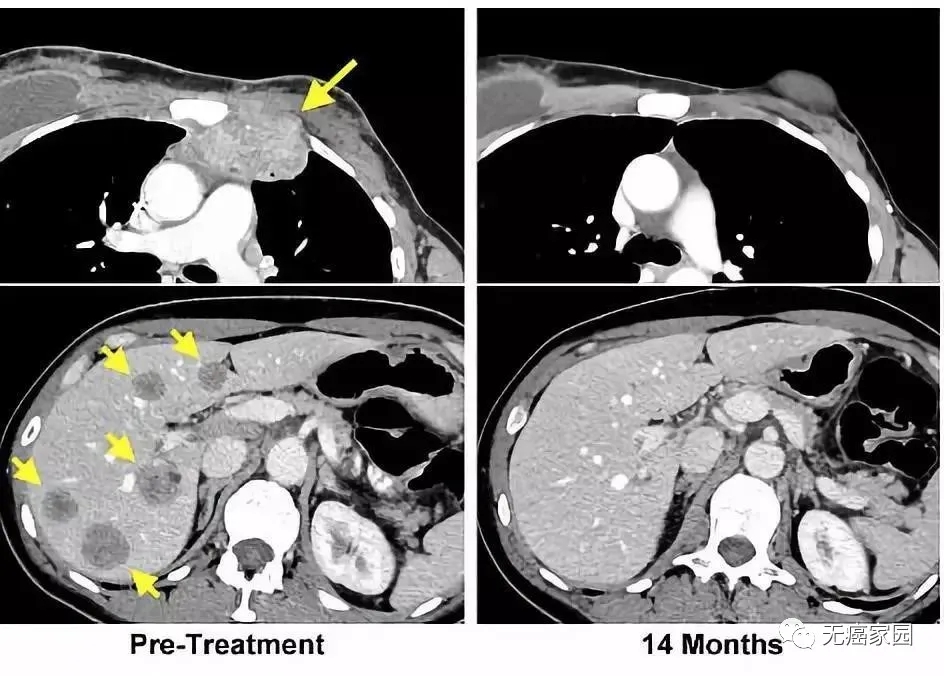

左图黄色箭头是治疗前肿瘤位置;右图是治疗结束14个月后的复查:肿瘤完全消失